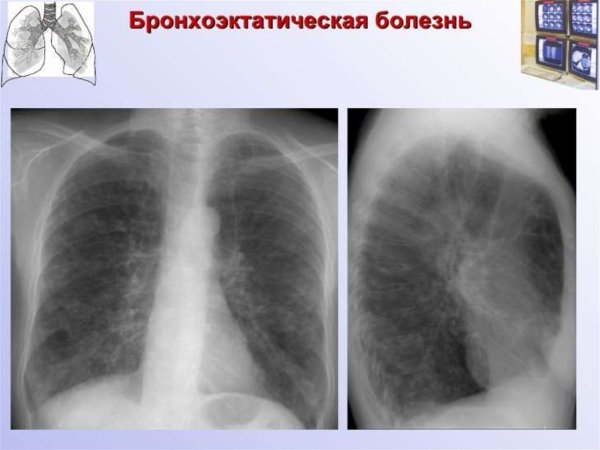

Деформированный легочный рисунок - это состояние, при котором наблюдается изменение обычного внешнего облика легких на рентгенограмме. Такое отклонение может быть связано с различными заболеваниями и патологическими процессами, такими как хронические обструктивные заболевания легких, фиброз, опухоли или воспалительные процессы. Деформированный легочный рисунок может представлять собой уменьшение объема легочной ткани, нарушение архитектуры легочных сосудов или изменение контуров легочных полей. Раннее выявление и диагностика таких изменений могут помочь в раннем начале лечения и улучшении прогноза для пациента.

Синдром деформации легочного рисунка